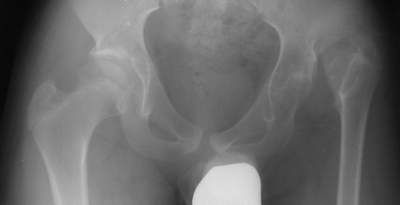

Это пока сегодня укорочение не воспринимается как проблема,по мере же развития дегенерации позвоночника оно станет существенной проблемой,поэтому ситуацию нужно исправлять комплексно.Я думаю,существует 2 варианта эффективного решения проблемы у этого пациента:

-тотальное эндопротезирование т/бедр.сустава(единственно приемлемый сегодня вариант в большинстве клиник,однако недешевый и не лишенный осложнений).

-двухэтапное лечение,включающее на 1-м этапе подвертельную вальгирующую остеотомию типа Шанца(ниже малого вертела примерно на 1,5см)с фиксацией бедра аппаратом Илизарова.При этом проксимальный отдел бедренной кости,будучи повёрнутым в процессе вальгирования,ложится под таз(создавая надёжную опору и убирая таким образом симптом Тренделенбурга и приводящую установку бедра).Для удобства можно использовать спице-стержневую компоновку аппарата(особенно в проксимальном отделе).Корригирующий угол(угол вальгирования)задается при установке проксимальной наружной опоры аппарата(полудуги),при этом нужно учитывать ещё и наличие у больного сгибательной установки бедра,приводящей к развитию гиперлордоза в поясничном отделе,с учетом чего необходимо создать кроме вальгусного угла ещё и умеренную антекурвацию.Через 1-1,5мес.,на втором этапе,с этим же аппаратом,осуществляется искусственный перелом н/3 бедра с последующей дистракцией до компенсации укорочения н/конечности.Функциональный результат после такой операции как правило устраивает больных в полной мере,т.к.комплексно устраняются болевой синдром,укорочение и порочная установка бедра с сохранением достаточного объёма движений.В сотрудничестве с к.м.н.В.А.Сафоновым имеем отдалённые результаты применения такой методики с 14-18 летними сроками наблюдения с отличными и хорошими функциональными результатами.К сожалению не могу продемонстрировать рентгенограммы из-за отсутствия в данный момент сканера. А.В.Сабсай,г.Днепропетровск.

Уважаемый Aleksey!

Эндопротезирование левого тазобедренного сустава позволит эффективно раебилитировать мальчика; особое внимание при формировании имплантационного ложа впадины (симметрично с контрлатеральным суставом),кроме того, при одномоментном низведении бедра возможны явления невропатии седалищного нерва, при высоких вывихах для профилактики такого вида осложнений операцию эндопротезирования делим на этапы - имплантация впадины, низведение бедра в аппарате наружной фиксации (2 опоры -крыло и нижняя треть бедра) 2 недели и повторное вмешательство по имплантации ножки.

С другой стороны, учитывая молодой возраст пациента, вполне эффективной будет опорная остеотомия бедра по Илизарову (подвертельная остеотомия с формированием точки опоры под нижний край впадины и кортикотомия в средней тери бедра для удлинения и нормализации оси). Лечение более длительное, до 3-4 месяцев в аппарате,но позволит оттянуть эндопротезирование на 10-15 лет.